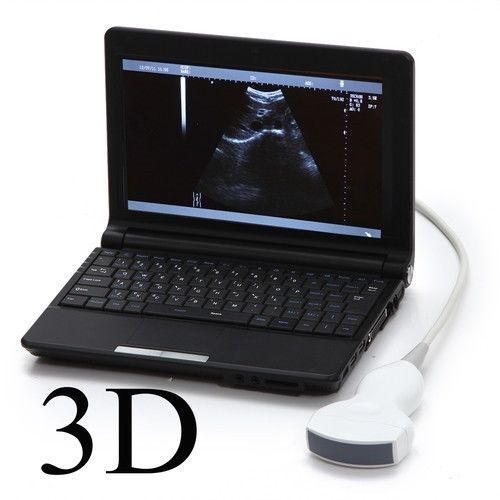

Laptop Ultrasound Machine, Notebook Digital Ultrasound scanner, 3.5 Convex probe

Sale price$ 1,648.00

Regular price$ 1,758.00